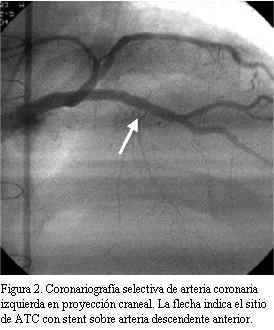

En buen estado de salud en marzo de 2004 (seis años y ocho meses después del TxC), instala astenia, adinamia y disnea clase funcional II-III (NYHA). Se realiza ecocardiograma transtorácico que mostró severa disminución de la FEVI. Se realizó cineangiocoronariografía (CACG) comprobándose lesión severa (75%) excéntrica del sector medio de arteria descendente anterior luego del origen de primera septal. Sector distal sin lesiones (figura 1). Se realiza angiograplastia transluminal coronaria (ATC) con implante de stent con sirolimus (Cypher) en forma primaria para arteria descendente anterior (figura 2). La estenosis residual fue 0%. La arteria descendente anterior presentó después de la ATC flujo TIMI III.

Tronco: fino, sin lesiones. Arteria descendente anterior: se ocluye inmediatamente luego del stent en unión de tercio medio y proximal. Lecho distal se llena tenuemente por circulación colateral homocoronaria. Malos lechos distales. Arteria circunfleja: severamente lesionada a neto predominio del sector distal. Leve mejoría con nitroglicerina intravenosa. Malos lechos distales. Arteria coronaria derecha: dominante, presenta severa enfermedad distal (figura 3).